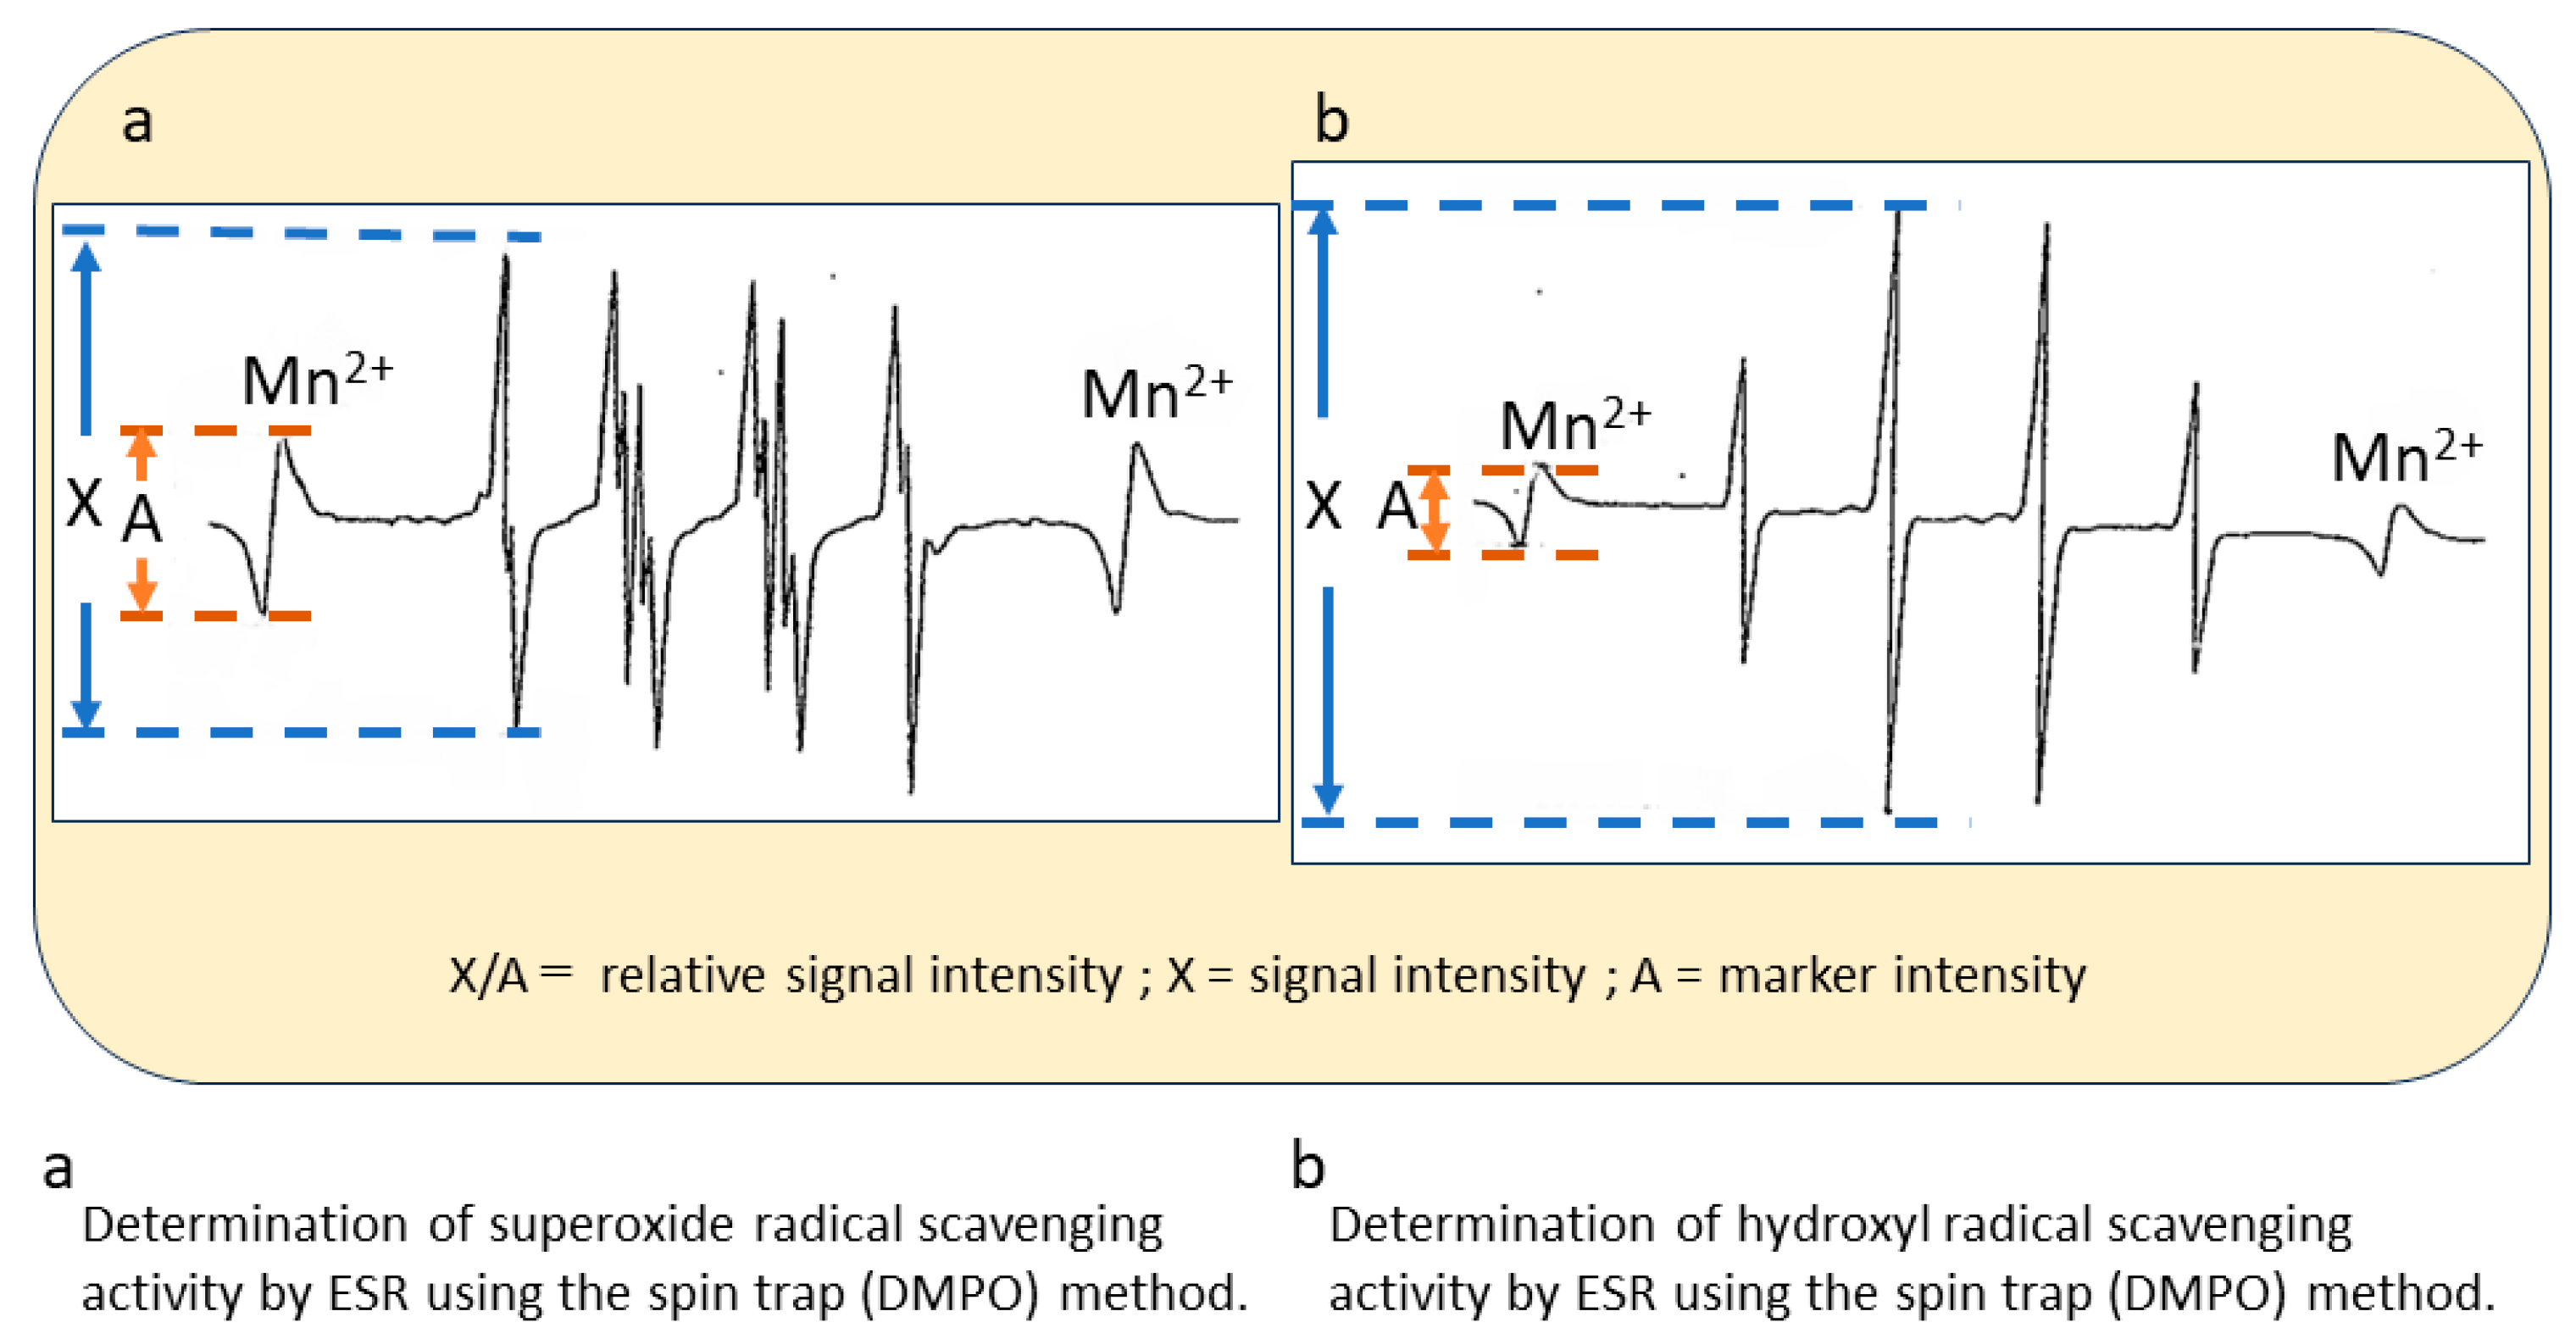

2.2. In Vitro ESR Method

3. Results